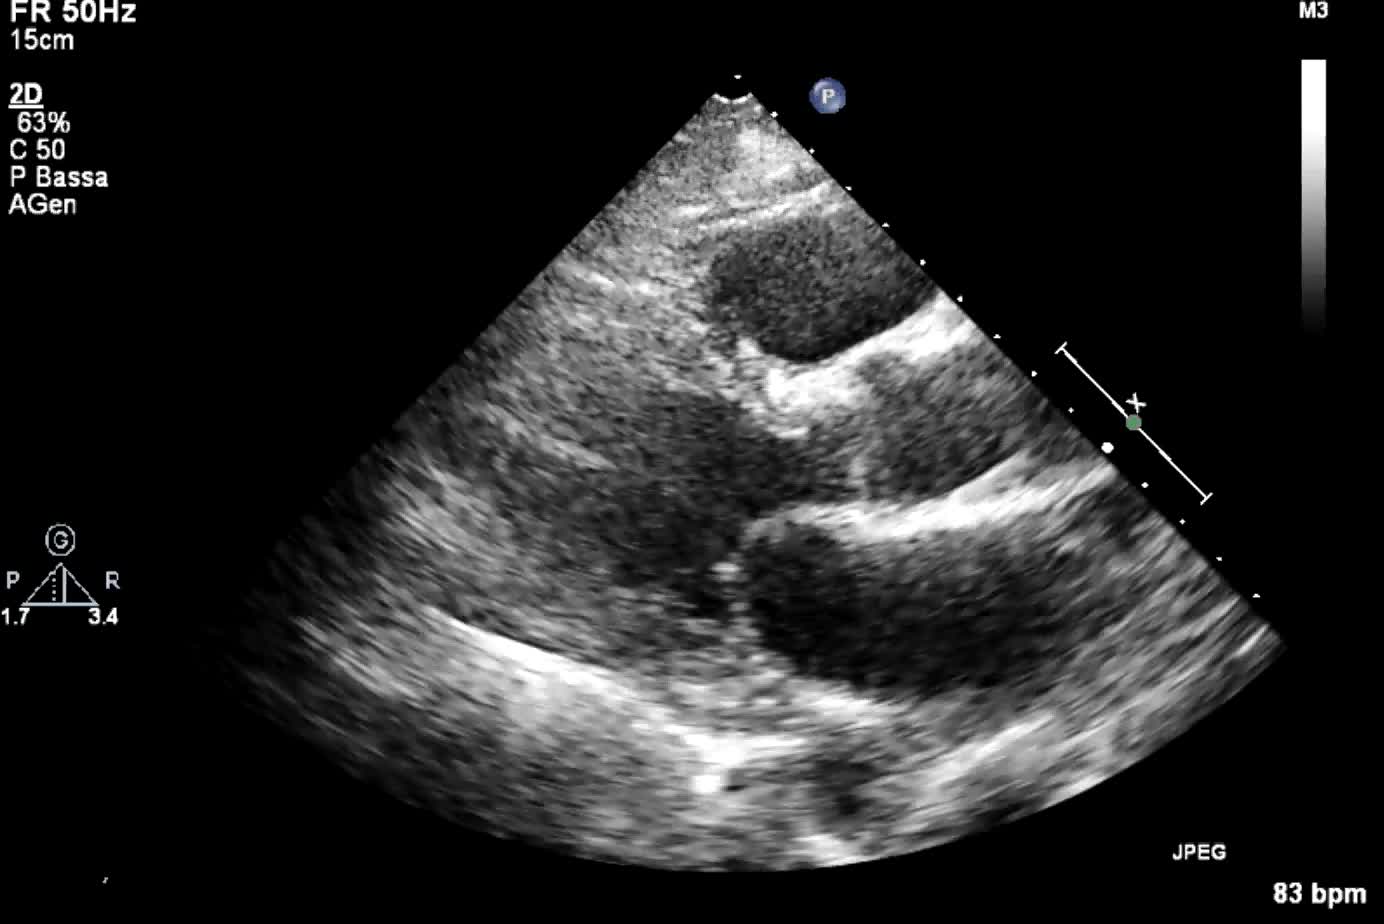

Titolo:

Protesi aortica meccanica malfunzionante

Autore:

Andrea Barbieri